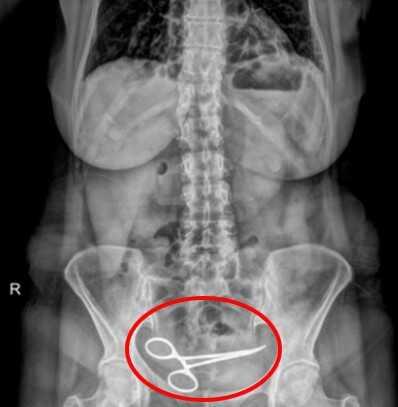

Ameliyatta unutulan makasla 8 ay yaşadı

Ankara'da tedavi gördüğü özel hastanede yapılan ameliyattan yaklaşık 8 ay sonra şiddetli karın ağrısı şikayetiyle başka bir hastaneye başvuran Şadiye Boyun'un çekilen röntgeninde karın bölgesinde ameliyat makası olduğu ortaya çıktı. Ameliyat sırasında unutulduğu belirlenen makas, yine ameliyatla alındı. Boyun, ameliyatı gerçekleştiren doktor ve hastane hakkında suç duyurusunda bulundu.

Burada çekilen röntgende Boyun'un ince bağırsağına takılı 12 santim boyunda makas olduğu görüldü. Ardından iddiaya göre, ameliyatın gerçekleştirdiği özel hastaneye haber verildi. Özel hastaneden görevliler geldi. Görevliler tarafından tekrar özel hastaneye götürülen Boyun'un röntgeni çekildi.